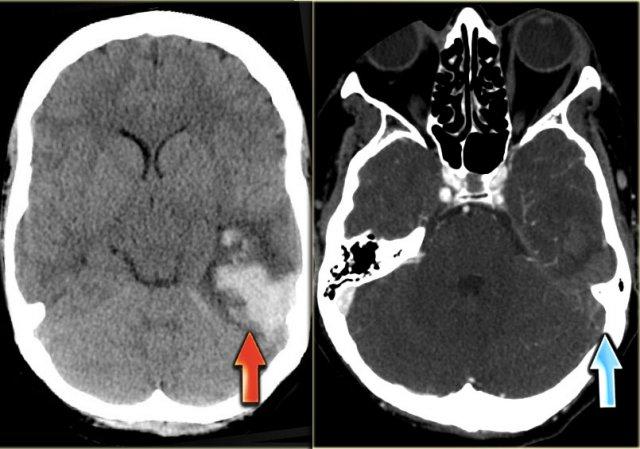

Hình ảnh bên trái là của một bệnh nhân có nhồi máu xuất huyết ở thùy thái dương (mũi tên đỏ).

Lưu ý xoang ngang tăng tỷ trọng do huyết khối (mũi tên xanh dương).